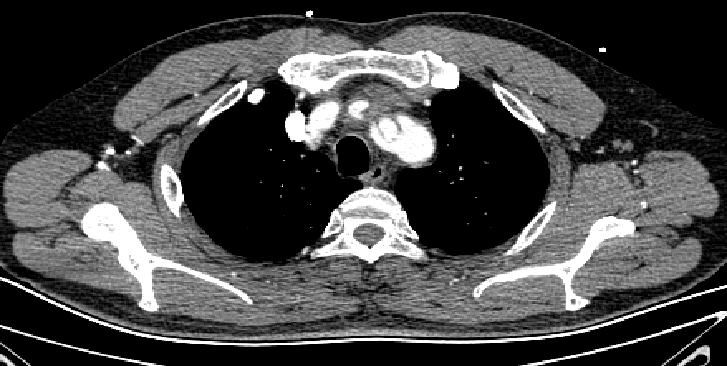

男性,44岁,慢性B型夹层。2010年12月行TEVAR术。

2013年5月发现RTAD,未处理。2015年2月死亡。